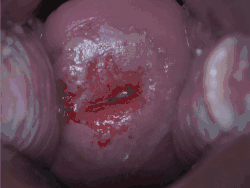

![]() | |

| Positive visual inspection with acetic acid of the cervix for CIN-1 | |